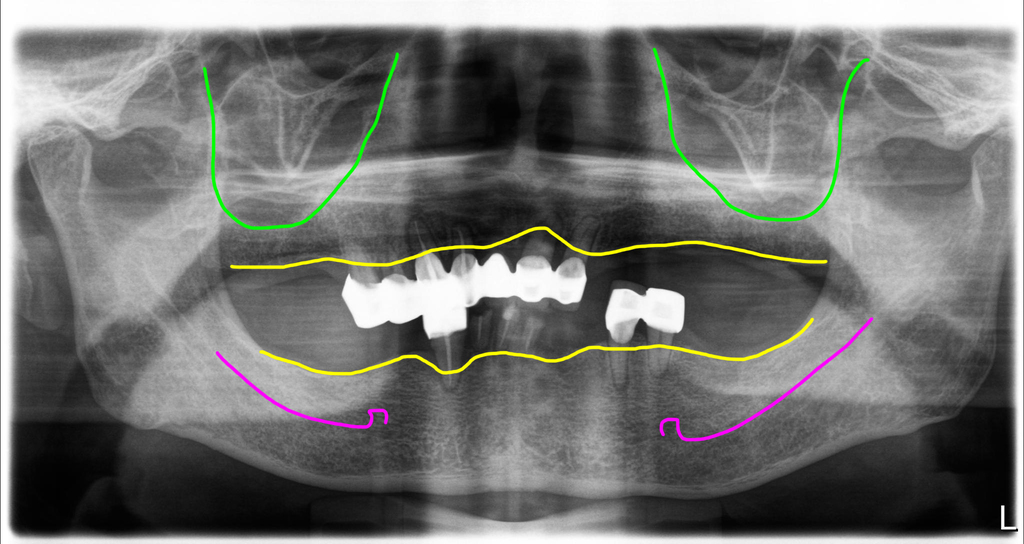

교합붕괴

고경이 낮아지면서 교합붕괴 아래턱이 뒤로 오버젯 커짐

치료전 고경소실로 교합붕괴

이전에 사용하던 틀니의 형태가 교합이 낮게 설정되어 있어 아래턱이 안으로 들어가 있었어요. 대부분의 환자는 이렇게 교합이 무너져 있어도 잘 느끼지 못하는 경우도 많습니다.

치료전 동영상에서 보시는 것처럼 남아있는 치아들이 모두 흔들리는 상태였습니다. 그리고 틀니를 끼고 문 상태에서도 오버젯이 너무 크고 아래턱이 왼쪽으로 치우쳐 있었고, 틀니를 제거하고 나면 더 심하게 아래턱이 왼쪽으로 더 이동하고 있었습니다.